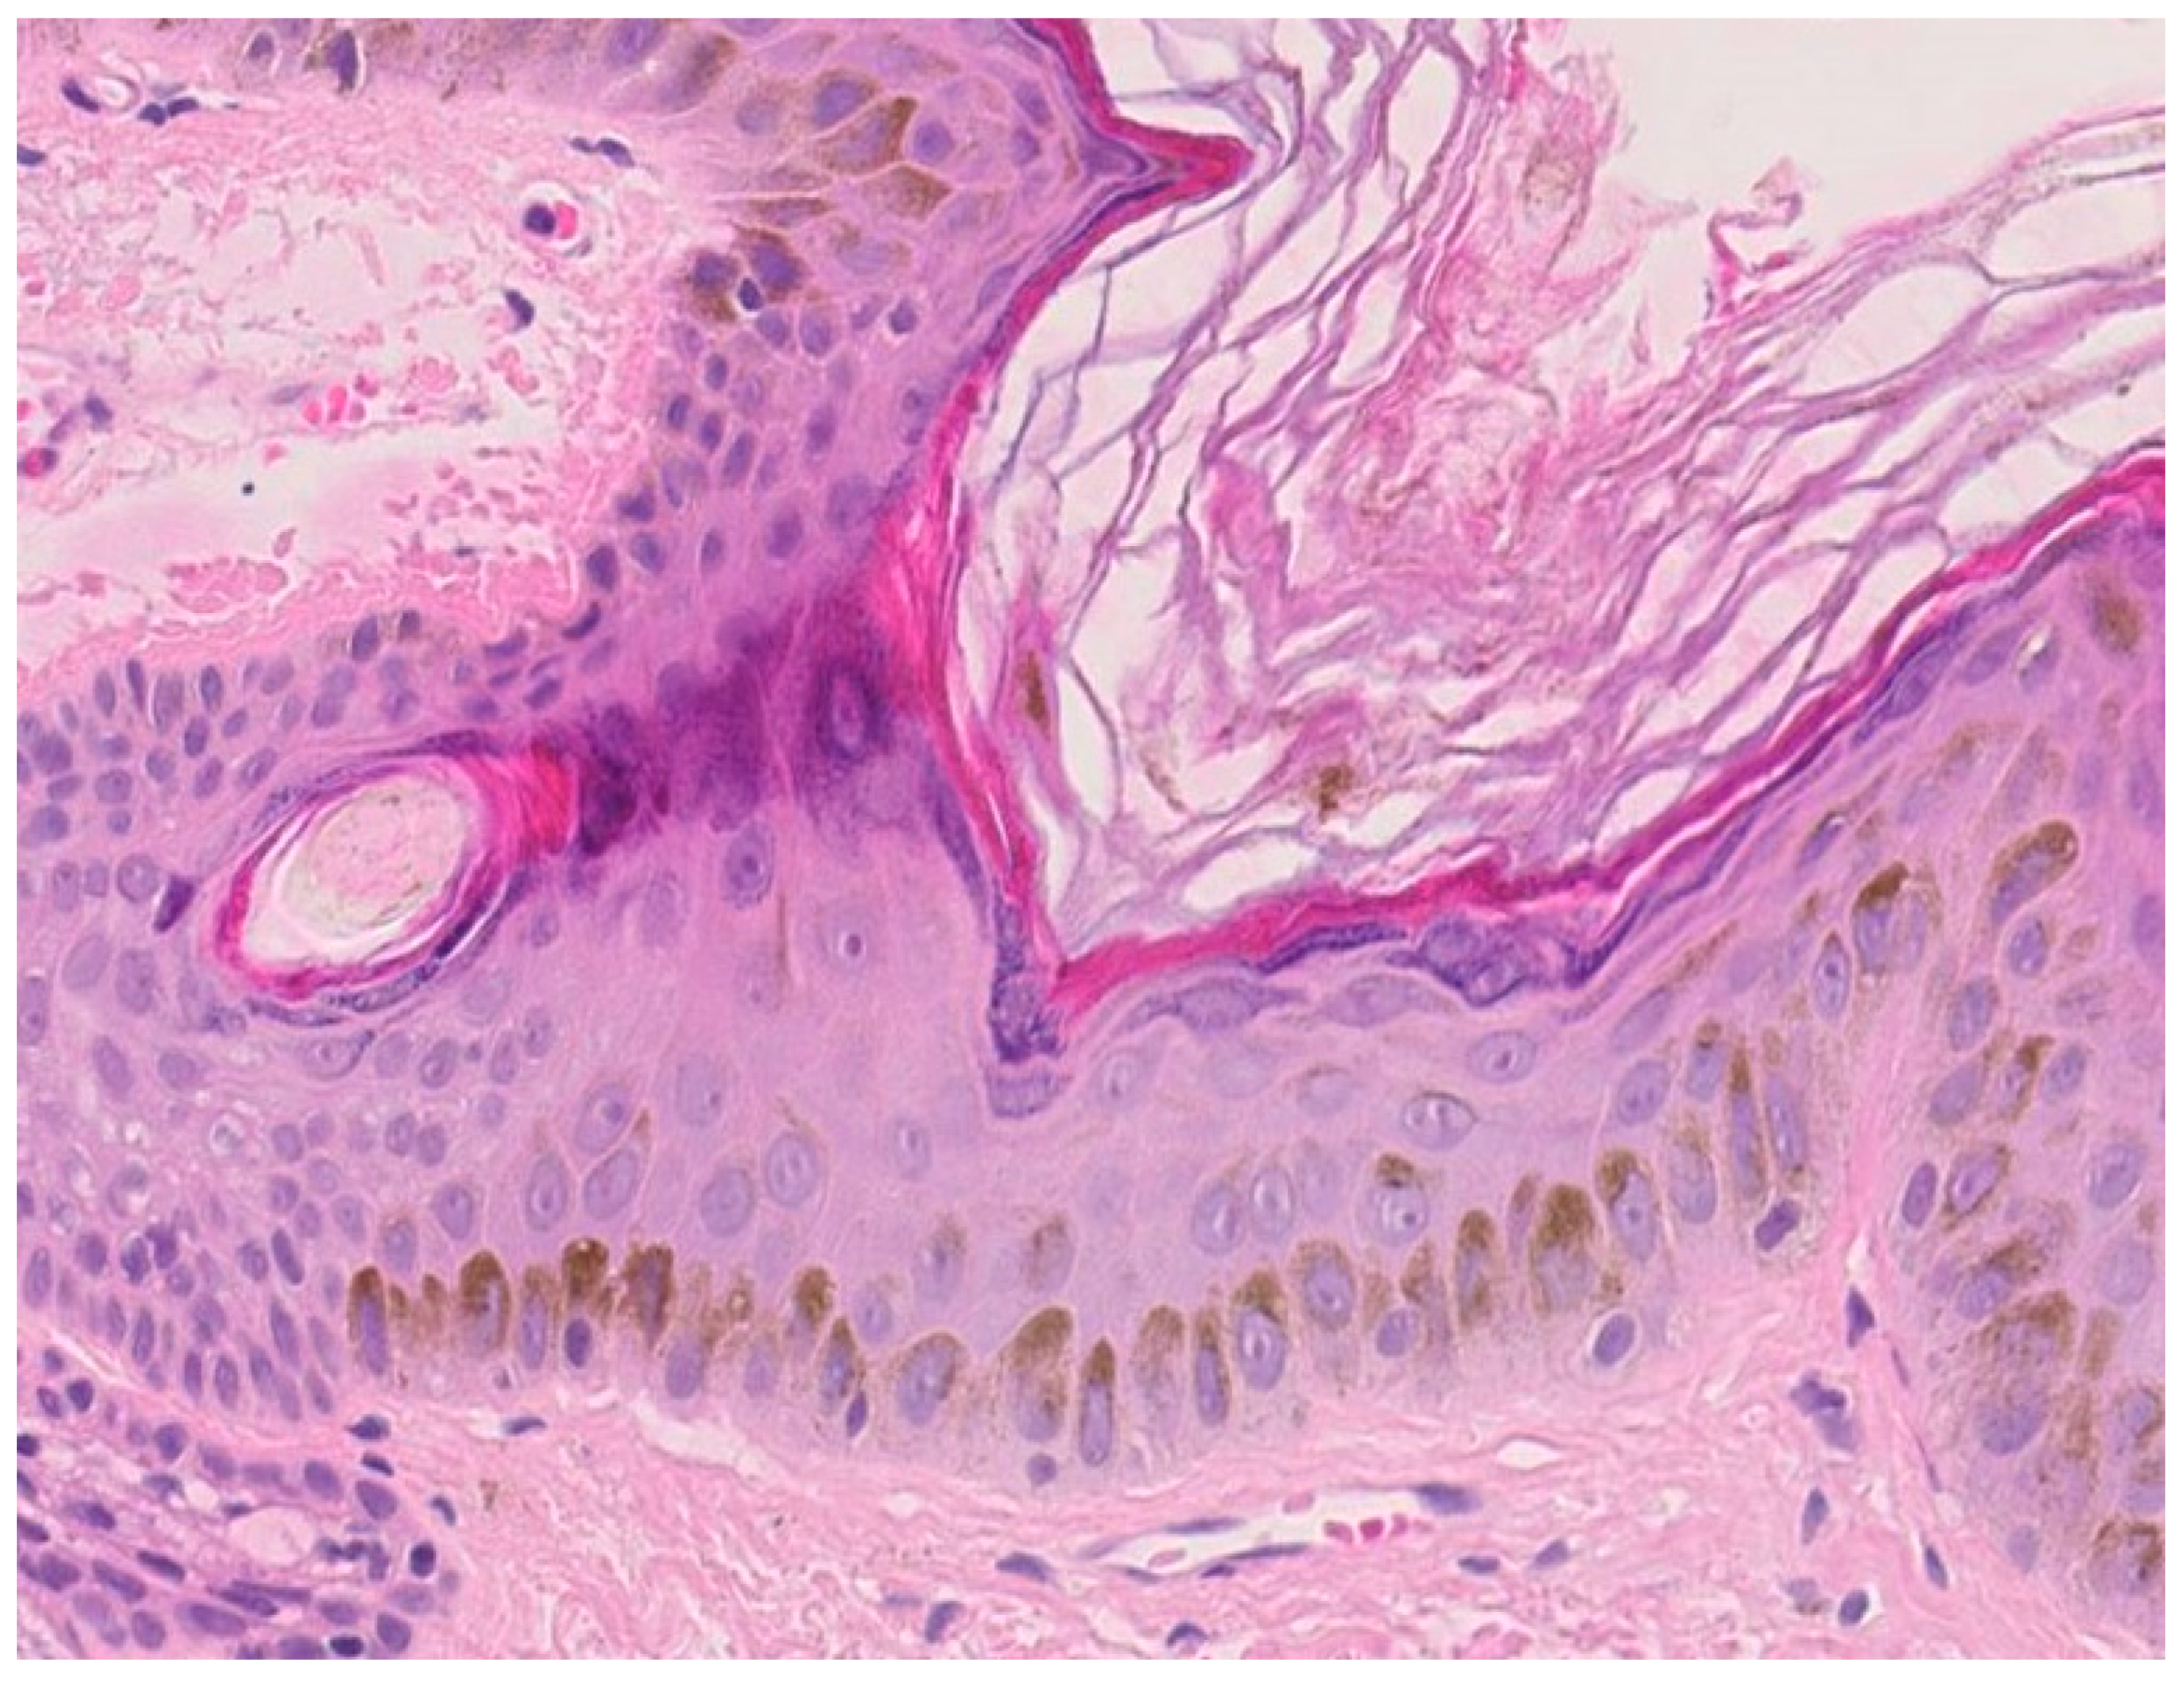

Melanin, the pigment elaborated by melanocytes, is another adaptive filter to UVR. Melanocytes are found between keratinocytes of the stratum basale, at the ratio of 1:10, and form the epidermal melanin units as a result of the relationship between one melanocyte and 30–40 associated keratinocytes. Melanin is synthesized in melanosomes—specialized, lysosome-like organelles. Mature melanosomes are transported along melanocyte microtubules within the pigment cell dendrites and transferred to neighboring keratinocytes [46]. These melanosomes form a cap over the cell nucleus to protect keratinocytes’ genetic material from being damaged by UVR (Figure 3) [47]. Epidermal melanin is a primary absorber of UVR, thus protecting the underlying epidermal and dermal elements. Melanin absorbs both ultraviolet and visible light and transforms the energy into heat through internal conversion. The absorption increases linearly in the range of 720 to 620 nm and then exponentially toward shorter wavelengths (300–600 nm). Upon UVB exposure, delayed pigment darkening appears in the skin. The tanning response is probably the most striking photo-protective mechanism against the detrimental effects of UVR exposure to the skin. Stimulation of the UV-dependent α-MSH-MC1R pathway activates the cAMP-CREB-MITF cascade in melanocytes, resulting in the synthesis of melanin and eventual transfer of melanosomes to keratinocytes for protection against UVR [48,49]. Epidermal (and follicular) melanocytes produce two types of melanin pigment, eumelanin and pheomelanin. Epidermal photoprotective barrier to UVR is based on the predominant pigment, eumelanin, which functions as a free radical scavenger with superoxide dismutase-like activity that reduces reactive oxygen species (ROS). Pheomelanin, instead, can generate ROS through UV-dependent and UV-independent pathways, exposing therefore fair-skinned individuals to an increased risk of melanoma [50].

Figure 3.

Human epidermis after solar irradiation (magnification × 120, HES stain). UVB light stimulates melanin secretion which acts as a built-in sunscreen. Epidermal melanin is a primary absorber of ultraviolet radiation, thus protecting the underlying epidermal and dermal elements.